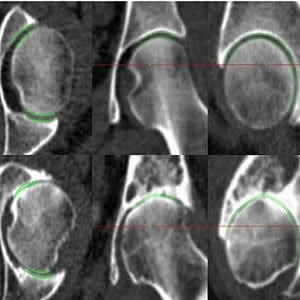

The semi-automated technique developed by Dr. Turmezei and his colleagues is called joint space mapping (JSM). The JSM algorithm analyses CT images to identify changes in the space between the bones of the joint in question, a recognised surrogate marker for osteoarthritis. After developing the algorithm with tests on human hip joints from bodies that had been donated for medical research, they found that it exceeded the current "gold standard" of joint imaging with x-rays in terms of sensitivity, showing that it was at least twice as good at detecting small structural changes. Colour-coded images produced using JSM illustrate the parts of the joint where the space between bones is wider or narrower.

Joint space in hip, knee and ankle joints as analyzed by the JSM algorithm.